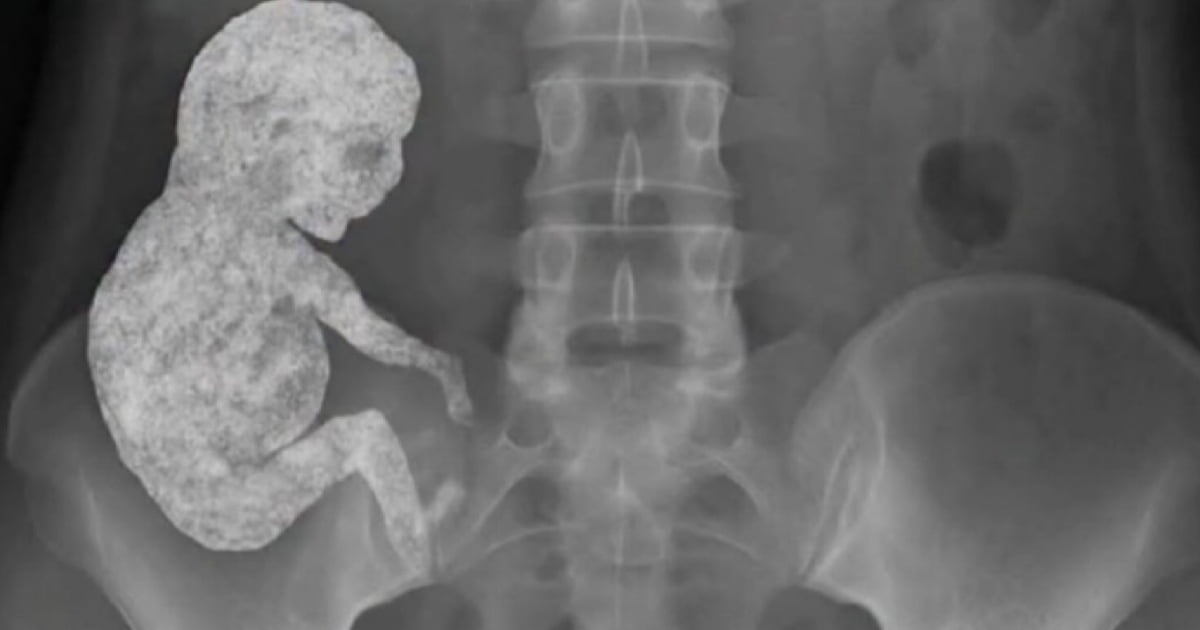

Случайная находка при обследовании. Возможно, плоду десятки лет.

Литопедион — это плод, который погиб при внематочной беременности, не был изгнан и со временем окостенел солями кальция. Организм воспринимает погибший плод как инородное тело и, не имея возможности его удалить, изолирует его, покрывая кальциевыми отложениями. Это своего рода защитная реакция, предотвращающая инфекцию и сепсис.

Чаще всего при внематочной беременности литопедион формируется в брюшной полости (абдоминальная беременность), где плод продолжил развиваться после разрыва маточной трубы.

Чаще всего выявляется случайно спустя годы или даже десятилетия (описаны случаи ношения литопедиона 40-60 лет) при рентгене, УЗИ или операции по другому поводу. Оно может длительно протекать бессимптомно или с неясными симптомами.